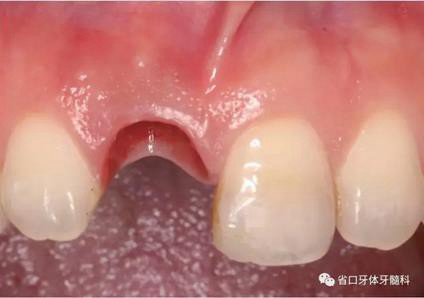

圖1 術(shù)前口內(nèi)照

圖2 術(shù)前口內(nèi)照

圖3 術(shù)前口內(nèi)照

(1)微創(chuàng)拔牙及即刻種植:術(shù)前拍攝口內(nèi)照及實(shí)施牙周基礎(chǔ)治療。常 規(guī)消毒鋪巾阿替卡因局麻下微創(chuàng)拔除上頜右側(cè)中切牙,搔刮拔牙窩及根尖肉 芽組織。探測牙槽骨唇側(cè)骨壁及鄰面牙槽嵴完整,牙齦無撕裂。不翻瓣下于上頜右側(cè)中切牙缺隙近遠(yuǎn)中中點(diǎn)的腭側(cè)牙槽骨及根方定位,按照逐級預(yù)備的原則,緊貼牙槽窩腭側(cè)骨壁制備種植窩洞,植入Zimer®3.7mm×13mm TSV種植體1顆,植入扭矩>35N·cm,以O(shè)sstell測量種植體的ISQ值為68。 種植體平臺(tái)位于唇側(cè)齦緣中點(diǎn)下3mm,與唇側(cè)骨壁內(nèi)側(cè)面形成的跳躍間 隙約2mm,置入Bio-Oss®細(xì)顆粒骨粉0.25g,上愈合基臺(tái)關(guān)閉創(chuàng)口。術(shù)后 CBCT檢查顯示:種植體利用牙槽窩根方骨質(zhì)固位,緊貼牙槽窩腭側(cè)骨壁, 其唇側(cè)面與牙槽窩唇側(cè)骨壁的內(nèi)側(cè)面所形成的跳躍間隙(約2mm)可見顆 粒狀顯影物充填。牙槽窩的唇側(cè)骨壁及唇側(cè)倒凹無缺損穿孔。